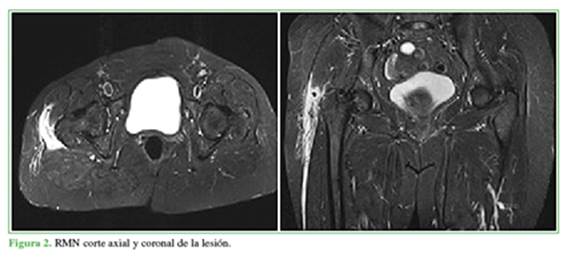

En el seguimiento, la paciente presenta un posoperatorio adecuado, no tuvo problemas con la herida quirúrgica y logró un buen control del dolor. La paciente presenta una evolución satisfactoria, inicialmente deambula con ayudas externas hasta que puede prescindir completamente de estas. En el control a los 6 meses, se documenta la buena evolución clínica; la paciente refiere que presenta dolor ocasional que no requiere el uso de analgésicos. No exhibe limitación alguna para sus actividades de la vida diaria, la cojera es mínima, no presenta Trendelemburg y su puntaje en el Harris hip score (HHS) es de 89,95. Tiene unos arcos de movimiento de cadera de 110º de flexión, extensión completa, aducción de 20º, abducción 15º, rotación externa de 30º e interna de 15º, con la última RMN de control sin lesiones recidivantes (Figura 4).